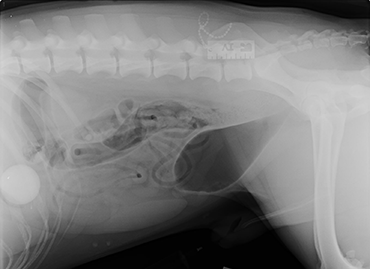

Our vets in Edinburgh were left stunned after an x-ray revealed that Pongo had ‘putt’ away a golf ball he must have found on a walk.

PDSA vet, Gemma Hepner, said: “We were primarily looking at the bladder, but the x-ray captured his stomach too – we could clearly see a foreign body in there.

“We knew it was a ball of some kind by the shape but couldn’t tell exactly what type. It was too big for him to pass and there was a real risk it could cause a fatal blockage in his stomach or his intestines if it were to move, so we had to operate to remove it.”